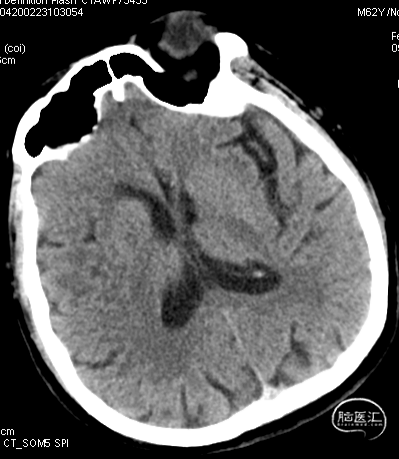

急诊颅脑CT+CTA:无脑出血,ASPECTS评分:7分;CTA示右侧M1闭塞。

急诊颅脑CT+CTA

急诊颅脑CT+CTA:多发腔梗,ASPECTS评分:8分;CTA示右侧M1闭塞。